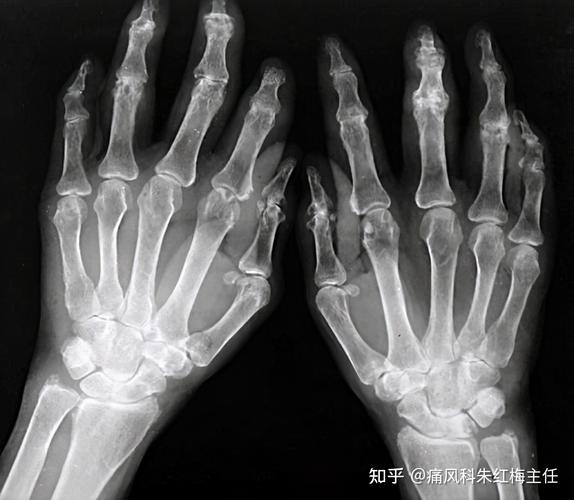

- 骨侵蚀:这是RA最具特征性的影像学标志,也是诊断RA的关键标准之一,侵蚀灶的特点是:

- 位置:通常出现在关节边缘(非承重面),特别是肌腱、韧带和关节囊的附着点附近。

- 形态:表现为边缘清晰、锐利的骨质缺损,可呈“虫噬状”或“穿凿样”。

- 好发部位:手指的近端指间关节和掌指关节,以及腕关节(尤其是桡尺远侧关节和腕骨间关节)是最常受累的部位,足部的跖趾关节也常见。

- 关节畸形:由于关节结构和韧带的破坏,导致关节半脱位和畸形,典型畸形包括:

- 尺侧偏斜:手指向小指侧偏斜。

- 天鹅颈畸形:手指的近端指间关节过伸,远端指间关节屈曲。

- 纽扣花畸形:手指的近端指间关节屈曲,远端指间关节过伸。

- 关节强直:晚期,严重的破坏和修复可导致纤维性或骨性强直,使关节活动完全丧失。

- 病理性脱位/半脱位:如指间关节半脱位。